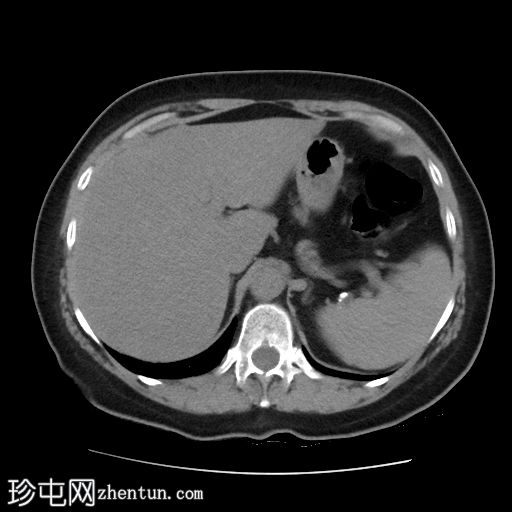

CT检查

轴位

平扫

既往行胃底折叠术部位位于膈肌上方,与透视检查结果一致。